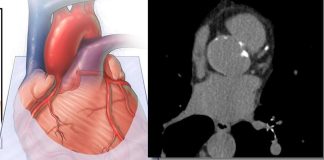

Detección precoz y acceso oportuno: factores clave para el tratamiento del...

En el marco de la Semana Mundial contra el Cáncer, especialistas en oncología refuerzan la importancia de la detección temprana y del acceso oportuno...

Cáncer en Chile: la carrera contra el tiempo que aún no...

En Chile, el cáncer sigue siendo un desafío para todos los actores del...

Día Mundial contra el Cáncer: Quién eres y donde vives no...

Para muchas personas, el cáncer no comienza con un diagnóstico, sino con un viaje de cuatro horas, una lista de espera que no avanza...

Día Mundial del Cáncer: tumores del páncreas lideran entre los más...

Cada 4 de febrero la Organización Mundial de la Salud (OMS) conmemora el Día Mundial contra el Cáncer, fecha que busca concientizar y educar...

La prevención y el diagnóstico temprano siguen siendo claves para enfrentar...

En Chile, cerca de 60 mil personas son diagnosticadas con cáncer cada año, una cifra que sigue en aumento y que refuerza la urgencia...

Día Mundial del Cáncer: Tendencia hacia la inmunoterapia subcutánea marcaría un...

Ante las proyecciones globales que alertan que la mortalidad por cáncer podría duplicarse hacia 2050, expertos destacan la urgencia de adoptar nuevas tecnologías...